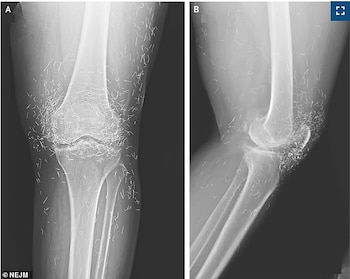

Luego de realizar una radiografía, los médicos hallaron cientos de pequeños hilos de oro incrustados en las rodillas de la paciente, consecuencia de un tratamiento alternativo que se realizó previamente, según difundió Daily Mail.

Sin embargo, el dolor se intensificó tras las sesiones. Motivada por este empeoramiento, decidió volver al hospital. Las imágenes médicas mostraron no solo las señales típicas de su artrosis, sino también varios fragmentos dorados alrededor de las rótulas, desde la tibia hasta el muslo.

Las complicaciones de los hilos de oro pueden ser serias. Entre los riesgos figura la posibilidad de que migren y dañen tejidos cercanos o provoquen infecciones persistentes en el organismo. Asimismo, los filamentos pueden dificultar la interpretación de radiografías, lo que complica detectar otras enfermedades articulares.